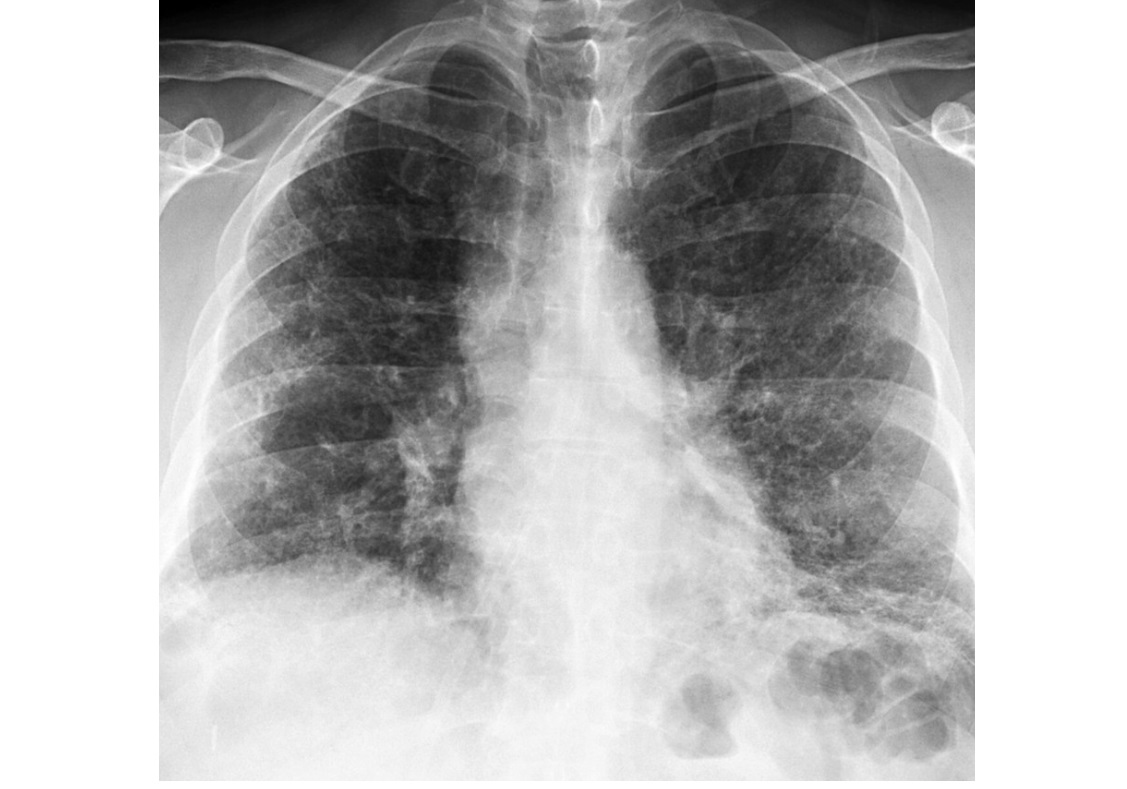

NSIP

lower lung zone predominant

CXR

bilateral, reticular opacities

CT

Absent (less) / microcystic honeycombing

Bilateral ground-glass &/or reticular opacities

Traction bronchiectasis/bronchiolectasis

Relative Subpleural sparing

peribronchovascular fibrosis

Most hunt for assocation/cause on CT

?dilated oesophagus - scleroderma

? joint disease - RA

?portcath/PICC - chemotherapy

sjorgens

HIV